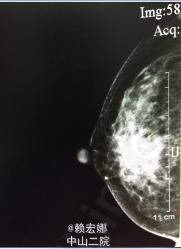

患者,女,2月前因发现右乳肿物

曾在局麻下行B超引导下右侧乳腺肿物穿刺活检术 +右侧腋窝肿物穿刺活检术,原发肿物:右乳12点钟乳晕旁见一大小为2.5*2.1cm的实性低回声团,右侧腋窝淋巴结3.5*1.9cm,术后病理:(右乳肿物、右腋窝肿物穿刺)乳腺浸润性导管癌,Ⅲ级。免疫组化:ER(-)、PR(-)、Her-2(3+)、Ki-67(+,40%)、P63(-)、E-cad(+)、Calponin(-)。

右侧乳腺癌诊断明确,予以TE新辅助化疗三次后,复查彩超:右乳12点钟乳晕旁见范围约1.4*0.9cm的实质性低回声团,边界不清,右乳10点钟方位见一大小为0.7*0.3cm的实性低回声团,边界清,形态规则,提示:1.右乳实性占位,多考虑乳腺Ca可能(较前次检查明显缩小);右乳实性低回声团,多考虑增生结节可能(BI-RADS Ⅱ类);双侧乳腺符合乳腺增生征象;2、双侧腋窝见淋巴结(右侧部分淋巴结淋巴门偏心)。患者经新辅助化疗后肿物明显缩小。患者完善相关检查,无明显手术禁忌症,遂在全麻下行右侧乳腺癌改良根治术+前哨淋巴结活检术,术后病理:1、(右侧乳腺浸润性导管癌癌灶剔除术后)残腔未见癌残留;2、乳腺及皮瓣四侧切缘,基底边缘及乳头未见癌浸润;3、(前哨、腋窝)淋巴结未见癌转移(0/3、0/14)。